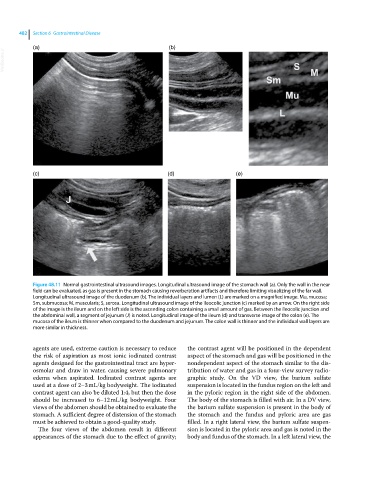

Figure 48.11 Normal gastrointestinal ultrasound images. Longitudinal ultrasound image of the stomach wall (a). Only the wall in the near

field can be evaluated, as gas is present in the stomach causing reverberation artifacts and therefore limiting visualizing of the far wall.

Longitudinal ultrasound image of the duodenum (b). The individual layers and lumen (L) are marked on a magnified image. Mu, mucosa;

Sm, submucosa; M, muscularis; S, serosa. Longitudinal ultrasound image of the ileocolic junction (c) marked by an arrow. On the right side

of the image is the ileum and on the left side is the ascending colon containing a small amount of gas. Between the ileocolic junction and

the abdominal wall, a segment of jejunum (J) is noted. Longitudinal image of the ileum (d) and transverse image of the colon (e). The

mucosa of the ileum is thinner when compared to the duodenum and jejunum. The colon wall is thinner and the individual wall layers are

more similar in thickness.